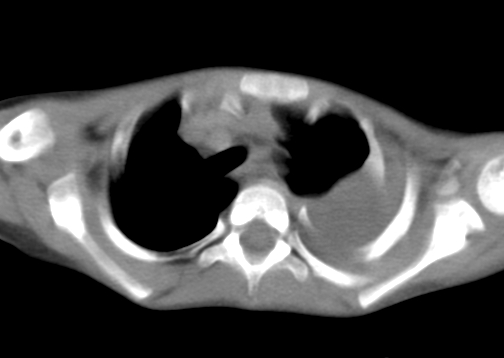

患儿 女 4岁,发热 咳嗽 胸透 考虑:左侧脓胸

左侧胸廓内见大量密实阴影,肺尖部尚有少量肺组织影,纵膈明显受压移位,肋骨未见明显受侵征象,虽然病人年龄较小,但如此大量的“积液”,还是要警惕,不同意一般感染,可结合穿刺脱落细胞学检查。

1)考虑左肺炎症感染。2)左侧大量胸腔积液。

左侧张力性大量胸腔积液压迫性肺不张、感染;建议治疗后复查。